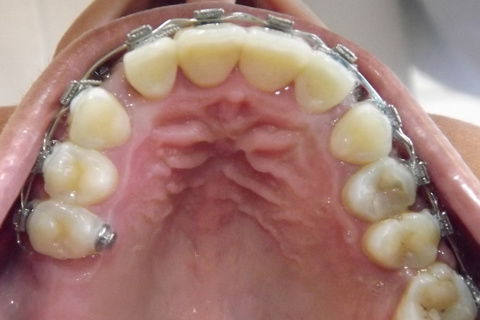

Foto após 22 meses.